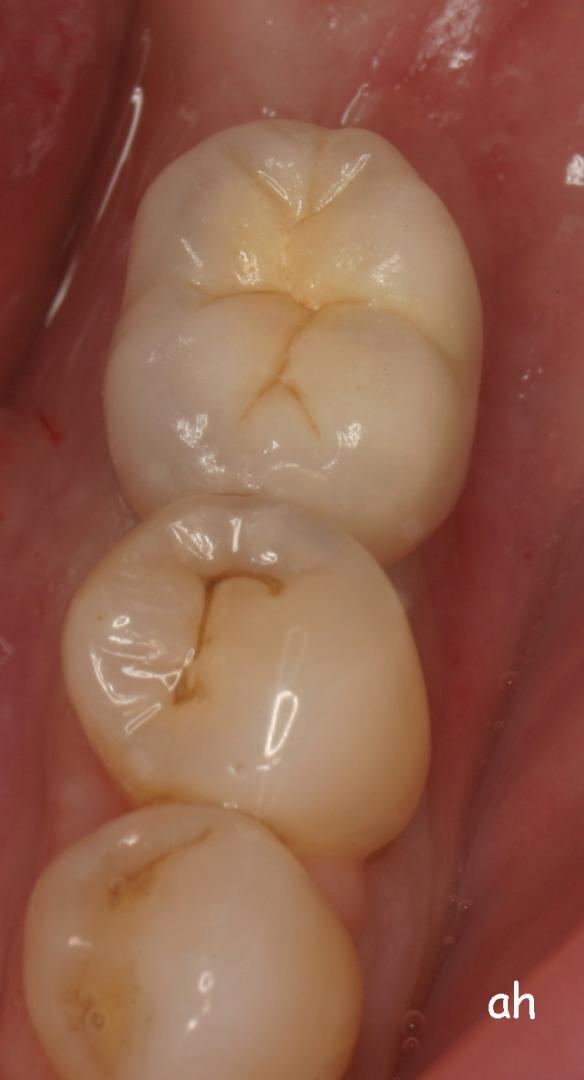

Exemple 2: Un implant remplaçant la racine d'une molaire inférieure gauche.

Exemple 2: La couronne en céramique scellée sur cet implant.